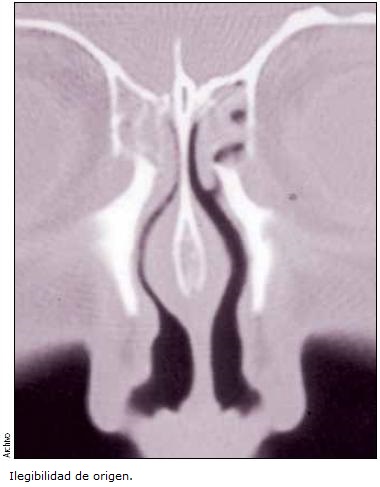

La tomografía computarizada de senos paranasales y órbita, simple y contrastada, mostró etmoides ocupado por imagen isodensa, lámina papirácea íntegra, órbita con edema en cono orbitario y pared medial, sin definirse la continuidad de músculo recto interno. Seno maxilar derecho etmoidal, esfenoidal y frontal con imagen isodensa correspondiente a hemorragia no activa.

El 24 de mayo de 2011, se realizó tomografía computada con ventana para hueso y tejido blando de órbita con cortes finos, mostrando discontinuidad del músculo recto medio derecho y nervio óptico derecho desplazado hacia la pared medial de órbita, sin definirse con exactitud la integridad del mismo, pared medial de órbita a nivel de celdillas etmoidales posteriores dehiscente, globo ocular en abducción total, edema periorbitario, concluyéndose que se trataba de complicación quirúrgica de turbinoplastía vía endoscópica con microdesbridador.

La paciente fue referida a Oftalmología de otro hospital; la nota de las 4:45 horas del 23 de mayo de 2011, señala que en conjunto con el Servicio de Radiología, se valoró la tomografía axial computarizada de órbita y senos paranasales tomada en su hospital de origen, la cual mostró hematoma retrobulbar de cavidad orbitaria derecha, ocupando el vértice orbitario, extendiéndose lateral y anteriormente, comprimiendo el recto interno, superior, inferior y nervio óptico, con solución de continuidad en la pared medial de la órbita derecha (lámina papirácea) y nivel que corresponde a líquido en zona circundante. Se estableció el diagnóstico de: hematoma retrobulbar derecho con neuropatía óptica isquémica grave derecha, estimando que el cuadro no era quirúrgico, debido a la pérdida visual y al tiempo transcurrido (más de 8 h de evolución).

Se debe precisar que la solución de la continuidad en la lámina papirácea del etmoides, indica que fue perforada por el microdesbridador, invadiendo la cavidad orbitaria y afectando las arterias etmoidales, lo que generó el hematoma retrobulbar.